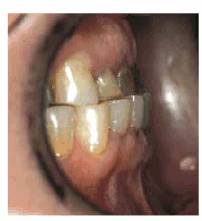

procedure can be seen in Figures 17-8A

and B 17-8C 17-8D 17-8E 17-8F 17-8G 17-8H and I, which show a 45-year-old man with

evidence of gingival and incisal abrasion, erosion, and abfraction. It is

Figure 17-8A and B: This 45-year-old man shows extreme tooth loss due to combination lesions both gingivally and incisally of abrasion, erosion, and abfraction.